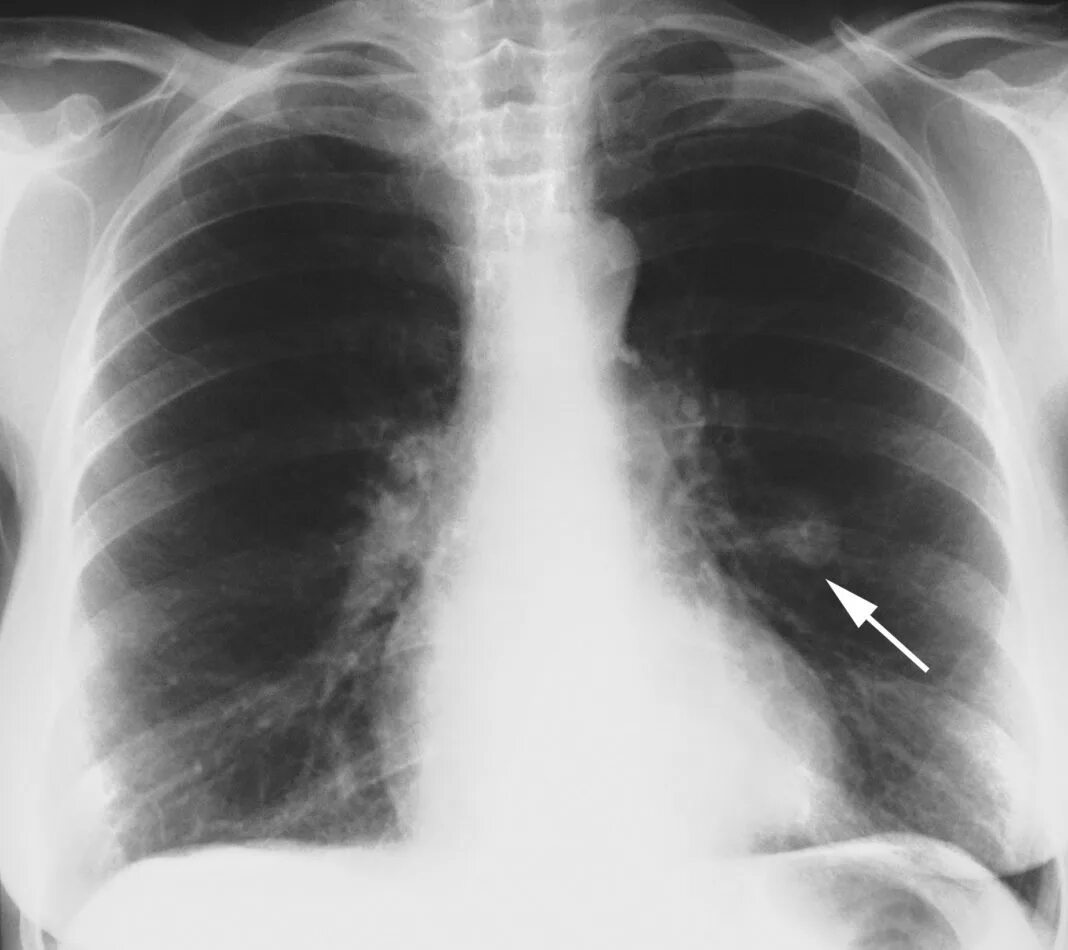

Единичные солидные узелки в легких